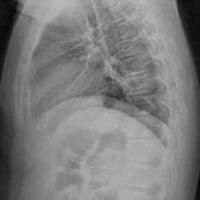

82岁老年女性,胸12椎体骨折。行球囊扩

82岁老年女性,胸12椎体骨折。行球囊扩张椎体成型术...

由 medjpg 发表于 2026-03-24 22:32